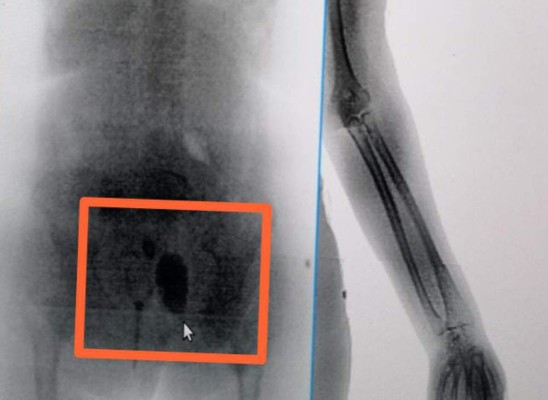

La fémina llevaba dos paquetes conteniendo marihuana que pretendía ingresar durante una visita al Centro Penitenciario El Pozo I en Ilama, Santa Bárbara, pero fue descubierta al pasar por el escáner.

El informe de las autoridades detalla que la droga estaba en el área rectal, dentro de un preservativo.